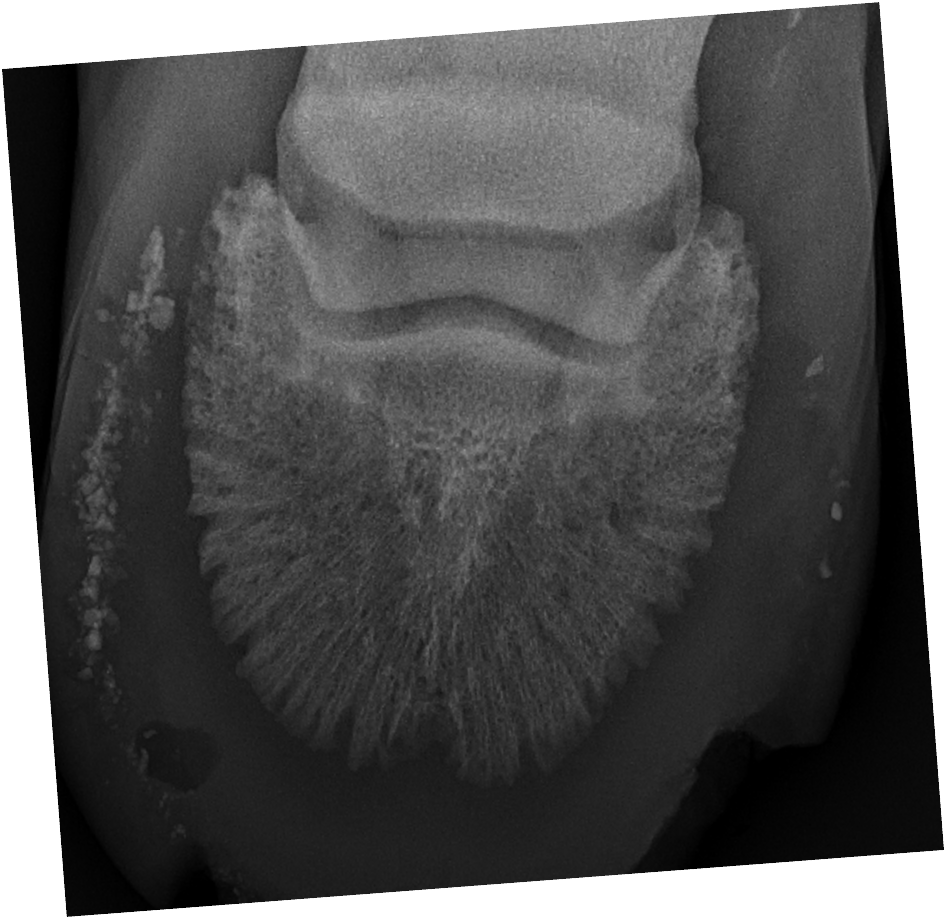

which OCD lesions are these in the dog

A = cd humerus

B = medial humeral condyle (elbow)

C = medial trochlear ridge (ankle)

D =lateral femoral condyle (knee)